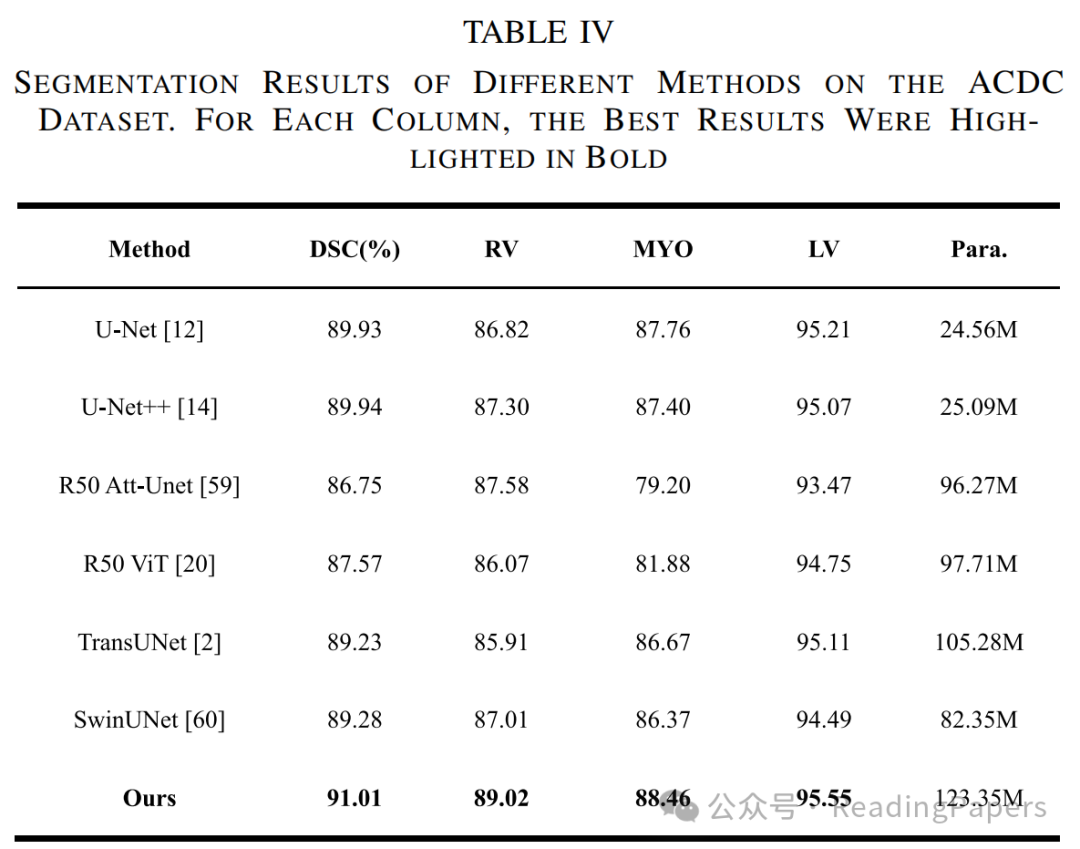

Transformer通过自注意力机制在医学图像处理中取得了显著进展,能够建模长距离语义依赖关系,但其缺乏卷积神经网络(CNN)捕捉局部空间细节的能力。本文提出了一种基于混合CNN-Transformer(MixFormer)特征提取骨干网络的新型分割网络,旨在提升医学图像分割的效果。MixFormer网络在下采样过程中无缝集成了Transformer和CNN架构的全局和局部信息。为了全面捕捉跨尺度的视角,作者引入了多尺度空间感知融合(MSAF)模块,有效实现了粗粒度与细粒度特征表示之间的交互。此外,作者还提出了混合多分支扩张注意力(MMDA)模块,用于在编码和解码阶段之间弥合语义差距,同时强调特定区域。最后,作者采用基于CNN的上采样方法来恢复低级特征,显著提高了分割精度。通过在多个主流医学图像数据集上的实验验证,MixFormer表现出卓越的性能。在Synapse数据集上,该方法达到了82.64%的平均Dice相似系数(DSC)和12.67 mm的平均Hausdorff距离(HD)。在自动心脏诊断挑战(ACDC)数据集上,DSC达到了91.01%。在国际皮肤成像协作(ISIC)2018数据集上,模型的平均交并比(mIoU)为0.841,准确率为0.958,精确率为0.910,召回率为0.934,F1得分为0.913。在Kvasir-SEG数据集上,平均Dice为0.9247,mIoU为0.8615,精确率为0.9181,召回率为0.9463。在CVC-ClinicDB数据集上,平均Dice为0.9441,mIoU为0.8922,精确率为0.9437,召回率为0.9458。这些结果表明,MixFormer在分割性能上优于大多数主流分割网络,如CNN和其他基于Transformer的结构。